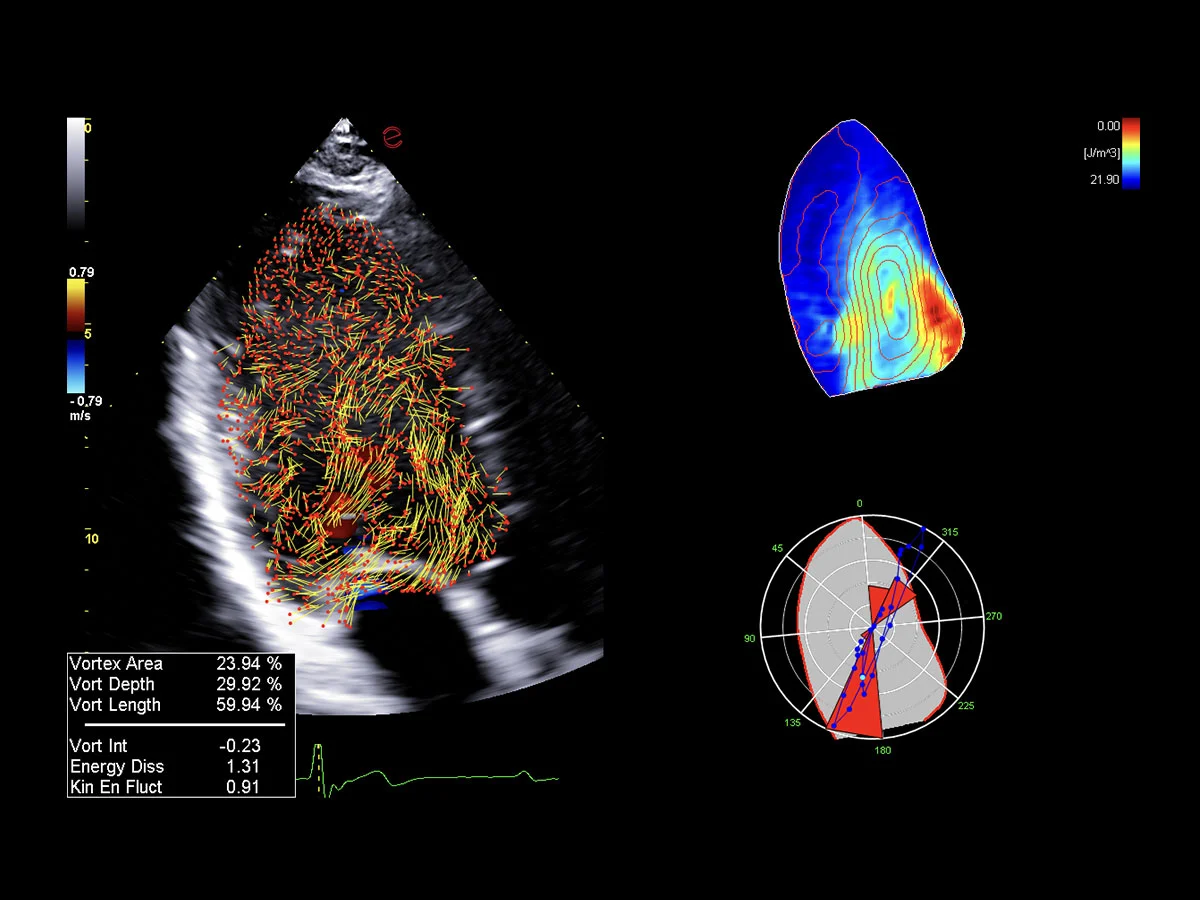

Innovative hemodynamic assessment with HyperDoppler

Esaote’s HyperDoppler technology provides an advanced visualization of intracardiac blood flow dynamics, offering clinicians an intuitive understanding of complex hemodynamics that goes beyond conventional Doppler imaging. By generating real-time vector maps, streamlines, and vortex formations, HyperDoppler enables the detailed assessment of diastolic function, ventricular dyssynchrony, and valvular abnormalities.

This unique flow visualization supports earlier detection of subtle dysfunction and increases diagnostic confidence, particularly in challenging cases such as heart failure, prosthetic valve evaluation, and structural heart disease. HyperDoppler’s zero-click, visually rich interface enables faster, more comprehensive exams, allowing cardiologists to make more informed clinical decisions.